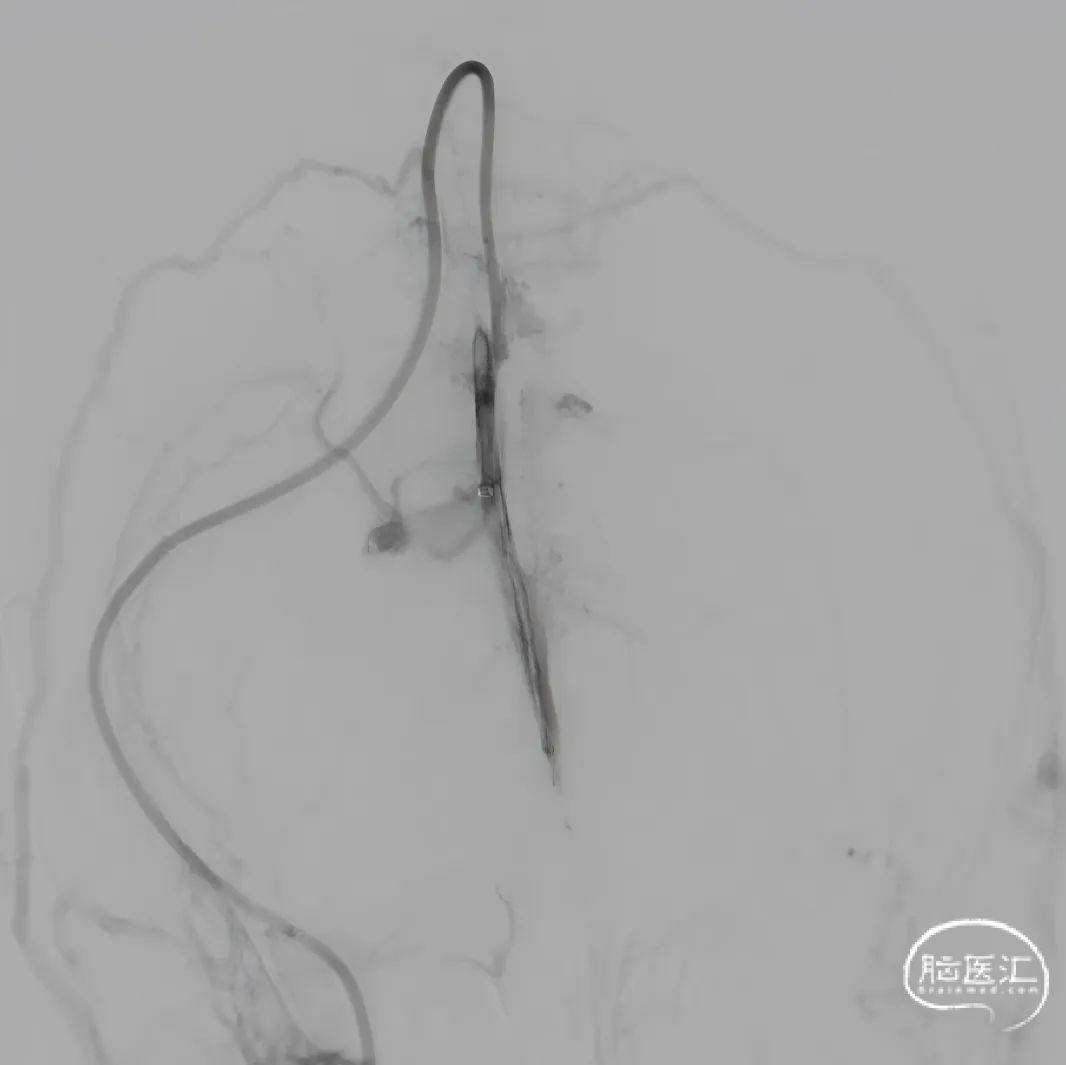

单纯抽吸难以实现良好再通,经300cm微导丝长交换送入115cm Navien™颅内支撑导管;选用5*30mm球囊扩张,碎栓。

球扩后造影,上矢状窦接触溶栓尿激酶20万U。

球囊扩张和接触溶栓后,再次经中间管反复抽吸后复查造影。

再次给予尿激酶10万U后复查造影。